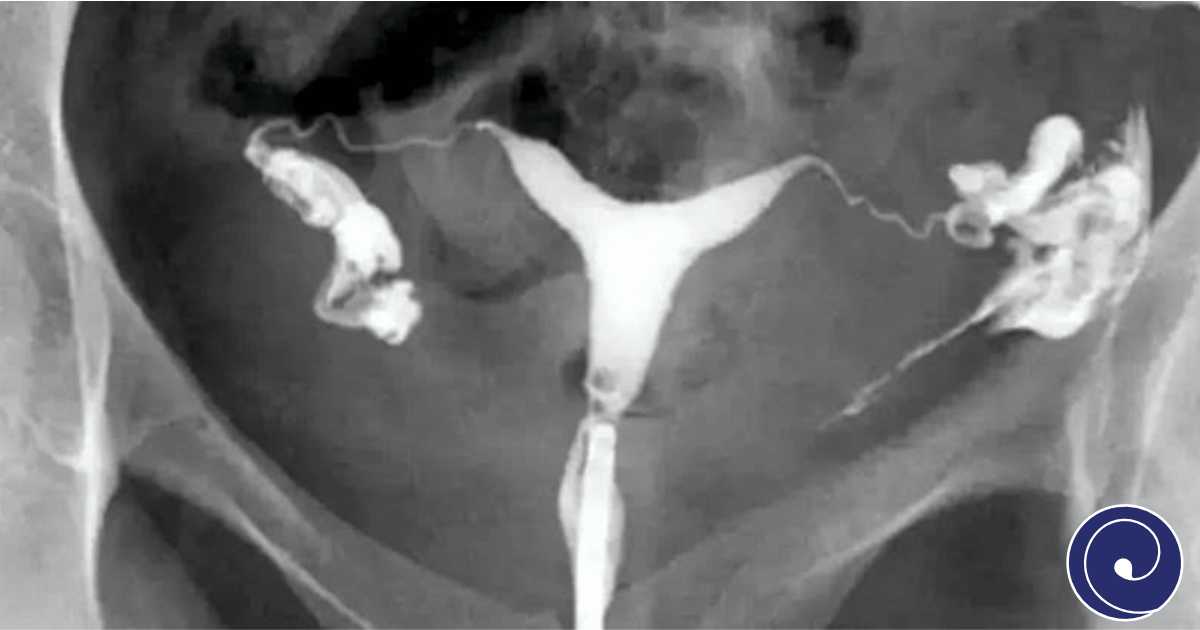

HSG (Histerosalpingografija)